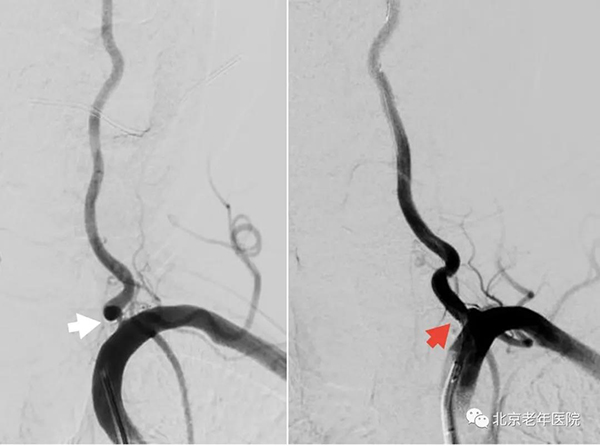

术中造影显示:左侧大脑中动脉M1段重度狭窄(白箭头)。全麻下同期行左侧大脑中动脉球囊扩张术及支架置入术(红箭头)。手术过程顺利,无不良事件发生,患者术后恢复良好。